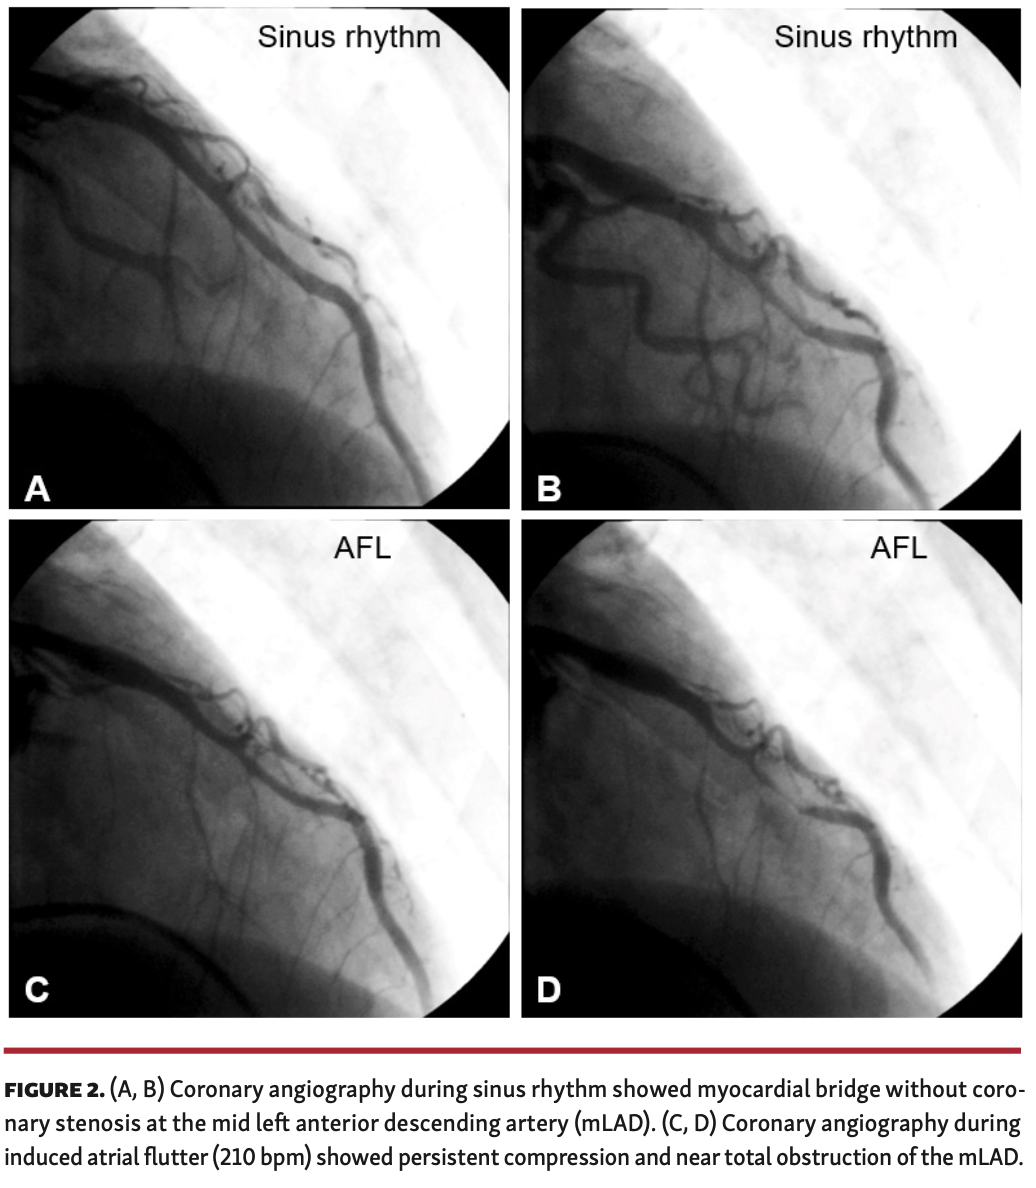

An electrophysiological study (EPS) was performed and atrial flutter (AFL) was induced similar to the initial ECG. Because his presenting symptom was angina, the patient was referred for coronary angiography at this point to rule out significant coronary disease. No significant coronary lesions were detected; however, a myocardial bridge was noted in the mid left anterior descending artery (mLAD) (Figures 2A and 2B). As the patient’s symptoms were combined with tachycardia, coronary angiography was repeated with concurrent EPS. During induced tachycardia, persistent compression and near total obstruction of the mLAD were seen (Figures 2C and 2D), and the patient complained of severe angina similar to his initial episode. Catheter ablation of the AFL was successfully completed, and at the 8-month follow-up visit, the patient remained free from both chest pain and palpitations.